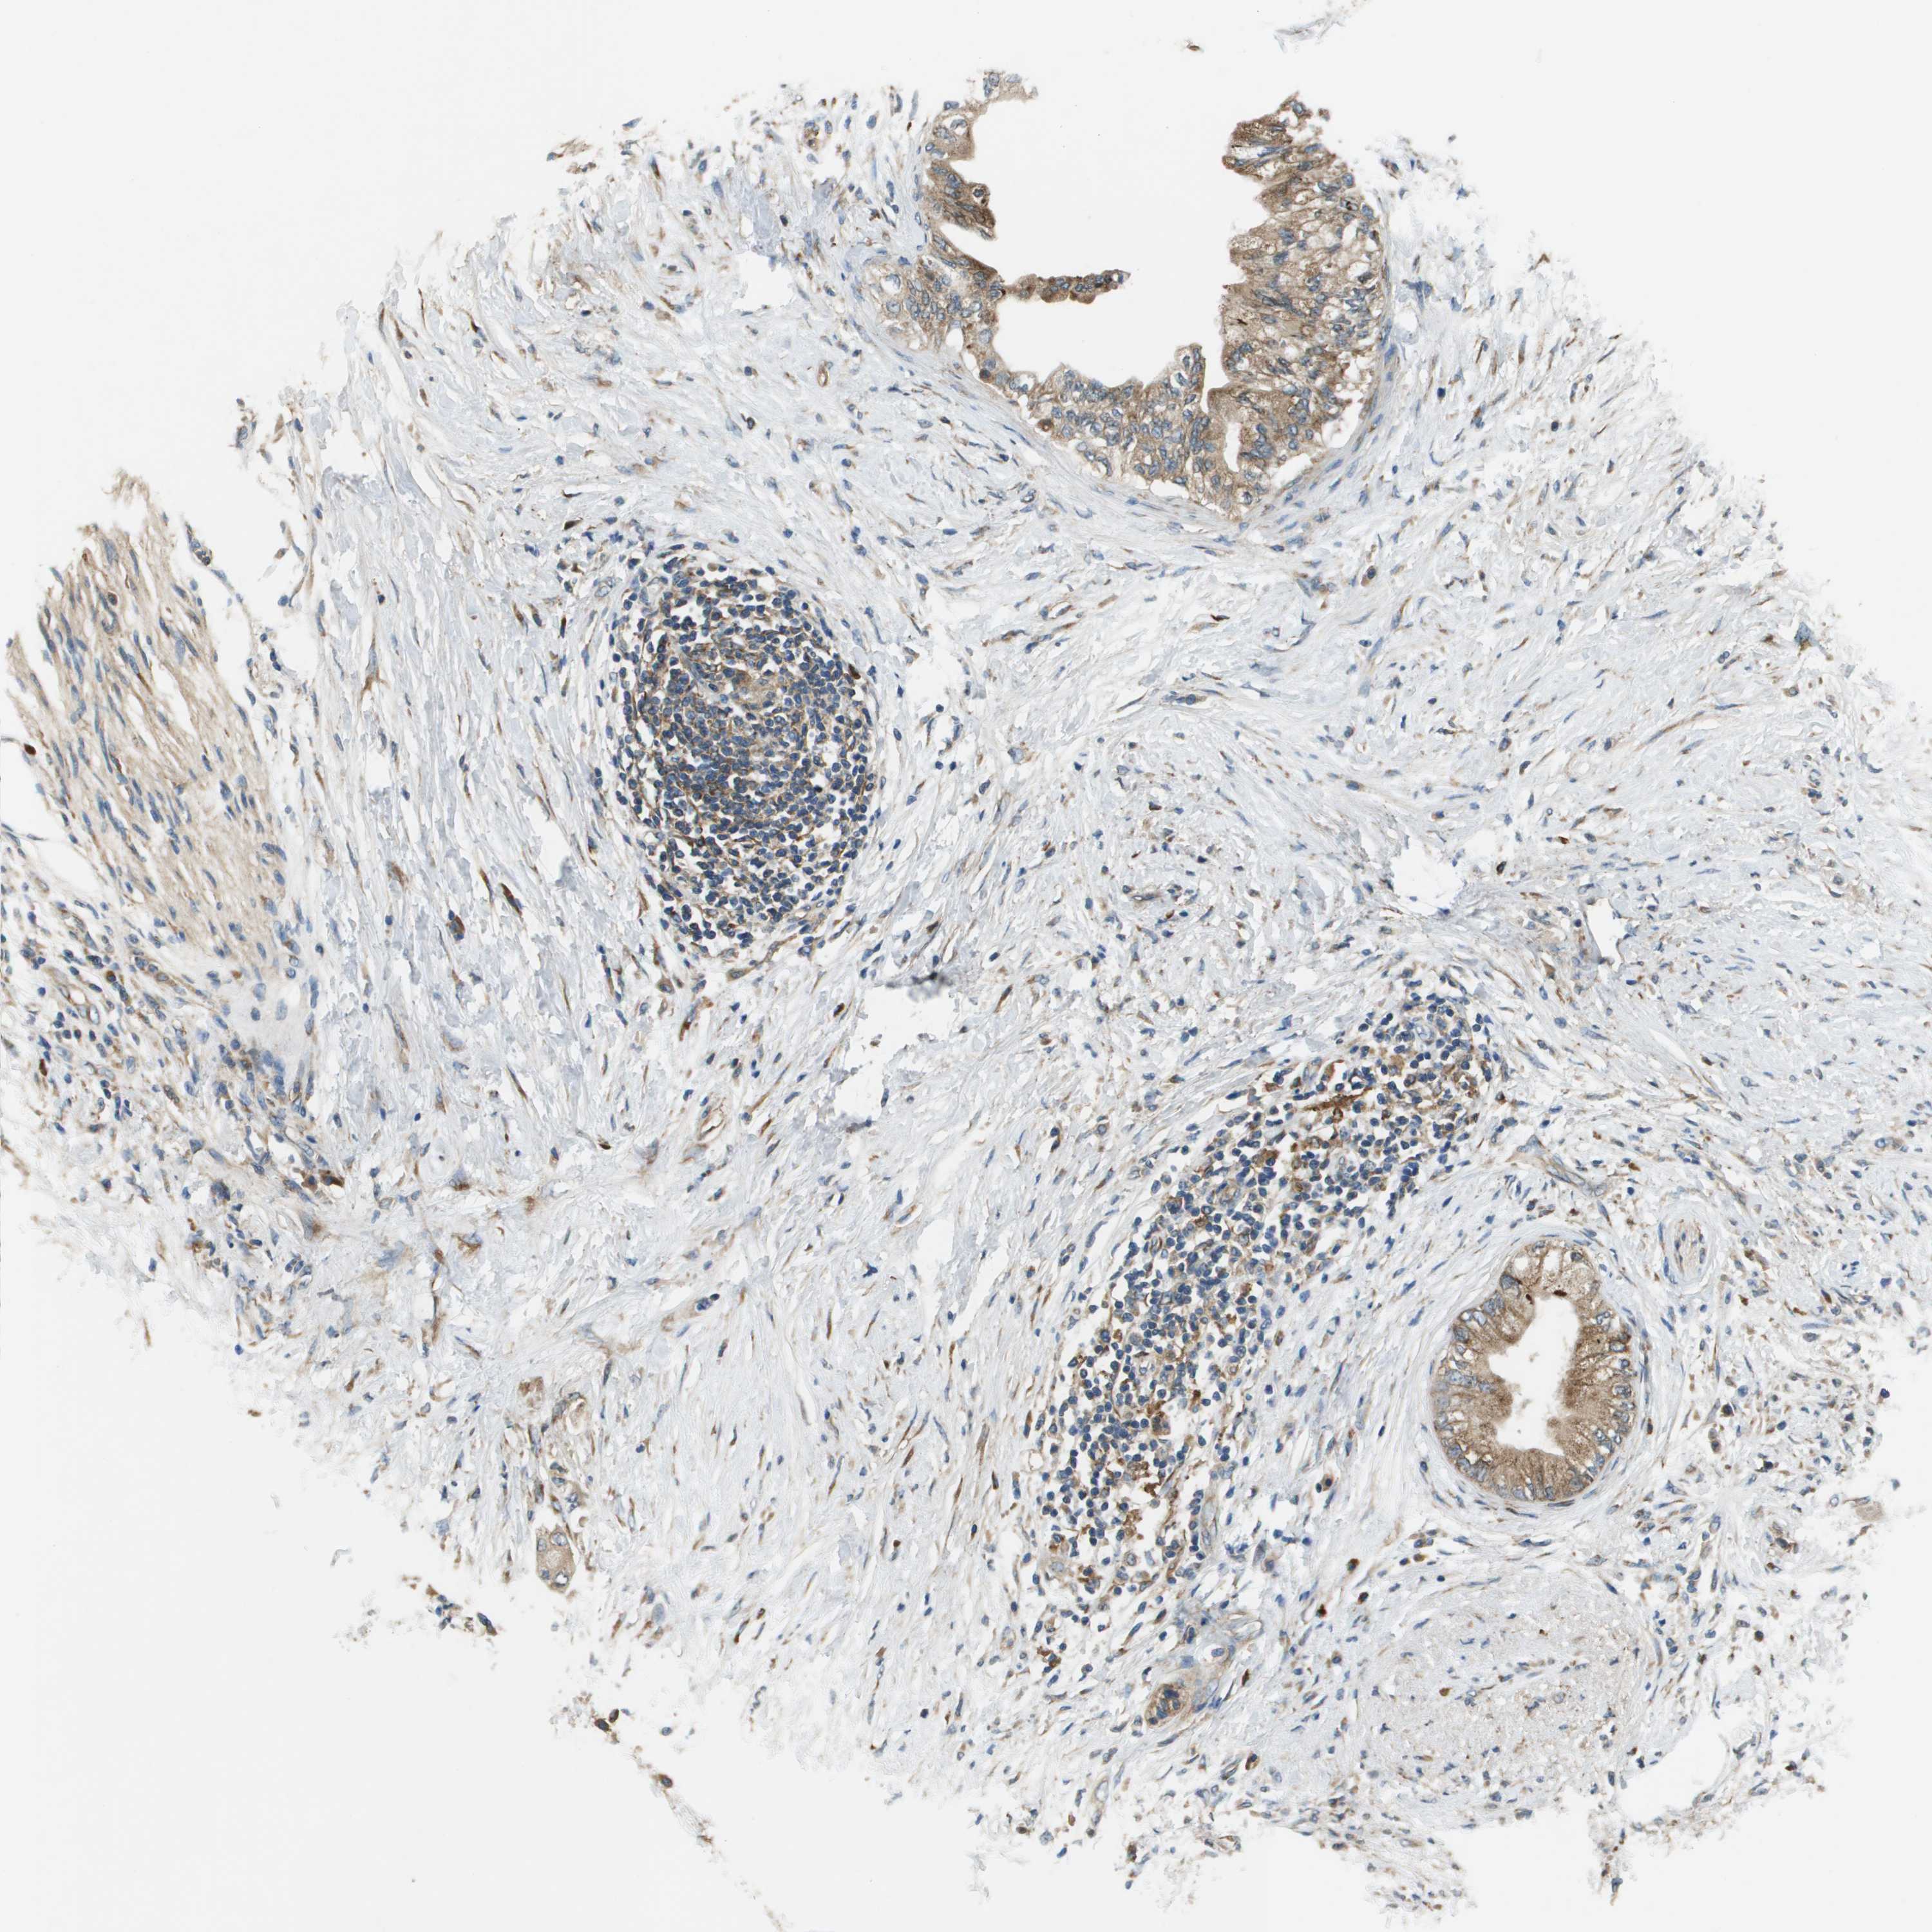

PANCREATIC CANCER - Protein expressioni

A mouse-over function shows sample information and annotation data. Click on an image to view it in a full screen mode. Samples can be filtered based on level of antibody staining by selecting one or several of the following categories: high, medium, low and not detected. The assay and annotation is described here.

Note that samples used for immunohistochemistry by the Human Protein Atlas do not correspond to samples in the TCGA dataset.

Antibody stainingi

Antibody staining in the annotated cell types in the current human tissue is reported as not detected, low, medium, or high, based on conventional immunohistochemistry profiling in selected tissues. This score is based on the combination of the staining intensity and fraction of stained cells.

Each image is clickable and will lead to virtual microscopy that enables deeper exploration of all samples and also displays staining intensity scores, fraction scores and subcellular localization as well as patient and tissue information for each sample.

Antibody HPA010645

Antibody HPA017055

Antibody HPA046639

Staining

High

Medium

Low

Not detected

Intensity

Strong

Moderate

Weak

Negative

Quantity

>75%

75%-25%

<25%

None

Location

Nuclear

Cytoplasmic/membranous

Cytoplasmic/membranous,nuclear

Adenocarcinoma, NOS

Adenocarcinoma, metastatic, NOS